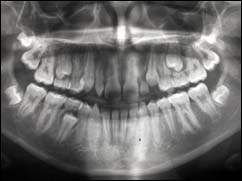

PANORAMIQUE :

Cette radio permet d’appréhender l’ensemble de votre dentition et des structures adjacentes.